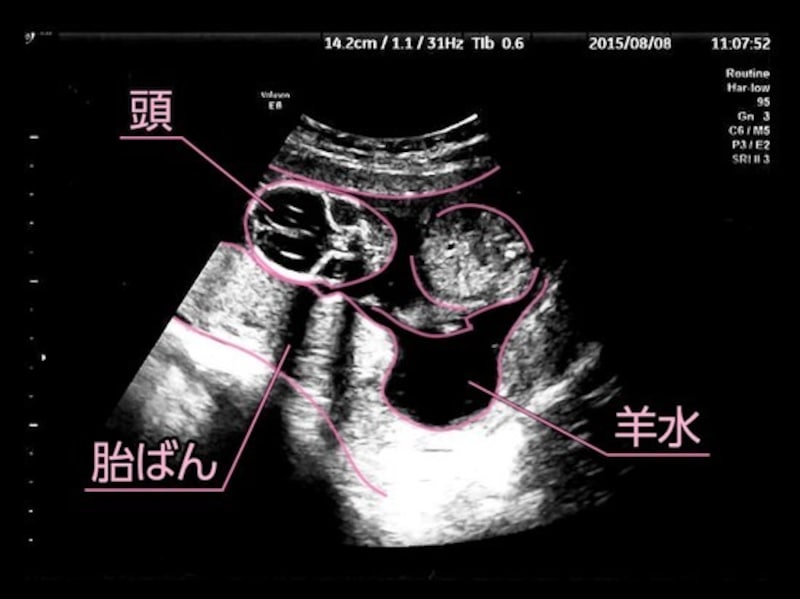

妊娠15週目の胎児の発達

- 妊娠15週目:受精から91~97日目

- 胎児の大きさ:CRL(頭殿長)が104~114mm

- 胎児の体重:40gほど

- 母体の変化:胎盤がほぼ完成し、体調が安定する人も

妊娠15週(15w)になると、皮膚が厚くなり、指紋ができたり、足のつめも完成してくるなど、体の細かい部分もどんどん作られています。体の大まかな組み立ては終わりましたが、全てがまだ未熟なので、これからは外部とのコミュニケーションを通して、それぞれの臓器や器官が成熟し、成長していきます。

赤ちゃんの顔の表情もバリエーションが増えてきて、難しい顔やしかめっ面もできるように。 閉じたまぶたの下では、目がゆっくりと動かせます。舌の上には味蕾(みらい)ができてきて、もうすぐ味も感じることができるようになります。

親指をチュッチュッと吸う吸啜反射(きゅうてつはんしゃ)ができるようになっています。胎児はおなかの中で顔を向けた方の指しかしゃぶりません。そして、これが利き手の始まりと推測されています。